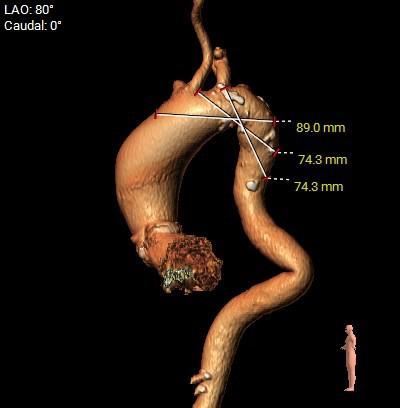

瓣环角度及弓角弓距

◇ 主动脉瓣环水平夹角52°,非横位心,主动脉弓角度较锐(43°)及弓距偏短;

◇ 外周入路血管走形迂曲,降主动脉有较锐夹角,主动脉弓,降主动脉,胸主动脉,腹主动脉有附壁钙化分布,血管内径可。